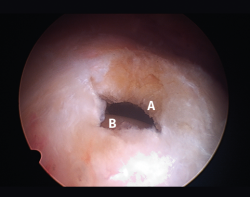

Figura 4. Rotura de supra- e infraespinoso en forma de L invertida con presencia de 2 capas. A: tendón supraespinoso; B: tendón infraespinoso; C: cabeza humeral.

Figura 5. Rotura de tipo C1. A: rotura pequeña de espesor completo del supraespinoso; B: cabeza humeral.

Sin embargo, las clasificaciones basadas en el tamaño de la rotura deben ser bidimensionales, ya que la visión unidimensional puede ser engañosa, al mostrar el tamaño de la rotura solo desde el plano anteroposterior(4). Por esta razón, proponemos el sistema de clasificación del manguito posterosuperior sugerida por Snyder, que aporta información no solo del tamaño, sino del número de tendones afectados y la presencia de tejido cicatricial(7). En las lesiones de tipo C1 la lesión atraviesa todo el espesor del tendón y en el eje transversal es pequeña y punzante (Figura 5). Las de tipo C2 son roturas de espesor completo pero la distancia entre los extremos de la rotura es menor de 2 cm con escasa retracción (Figura 6). En las de tipo C3 la rotura afecta en sentido transversal entre 3 y 4 cm con mayor retracción implicando 2 tendones (Figura 7). Y las de tipo C4 son la rotura masiva del manguito de los rotadores con una afectación de espesor completo de toda la anchura de 2 o más tendones asociando importante retracción (Figura 8).